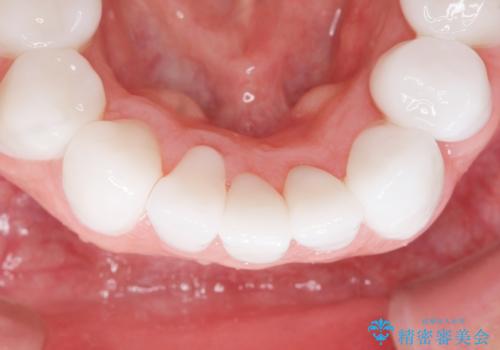

クラウンの色味・形態の修正や患者様のお仕事のご都合で来院できない期間があったことにより、予想より治療期間が長くなってしまいましたが、審美的な仕上がりにご満足頂けました。

矯正治療で歯並びを整えたいというのが歯科医師である私の本心でしたが、患者様の強いご希望によりオールセラミッククラウンによる補綴治療を行いました。

クラウンの色味に関して、自然な白さ(シェードA1~NW0.5)のクラウンを作製・試適したところ「もっと白くしたい」と希望され、当院で最も明度の高い色(シェードNW0)に修正しました。

被せ物の種類:オールセラミッククラウン スタンダード (シェード:NW0)